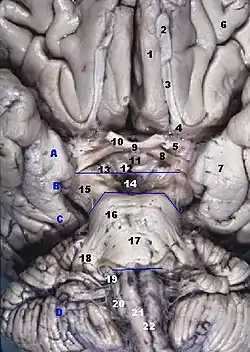

Human brainstem, anterior view. (Diagonal band of Broca not labeled, but anterior perforated substance is #5.) | |